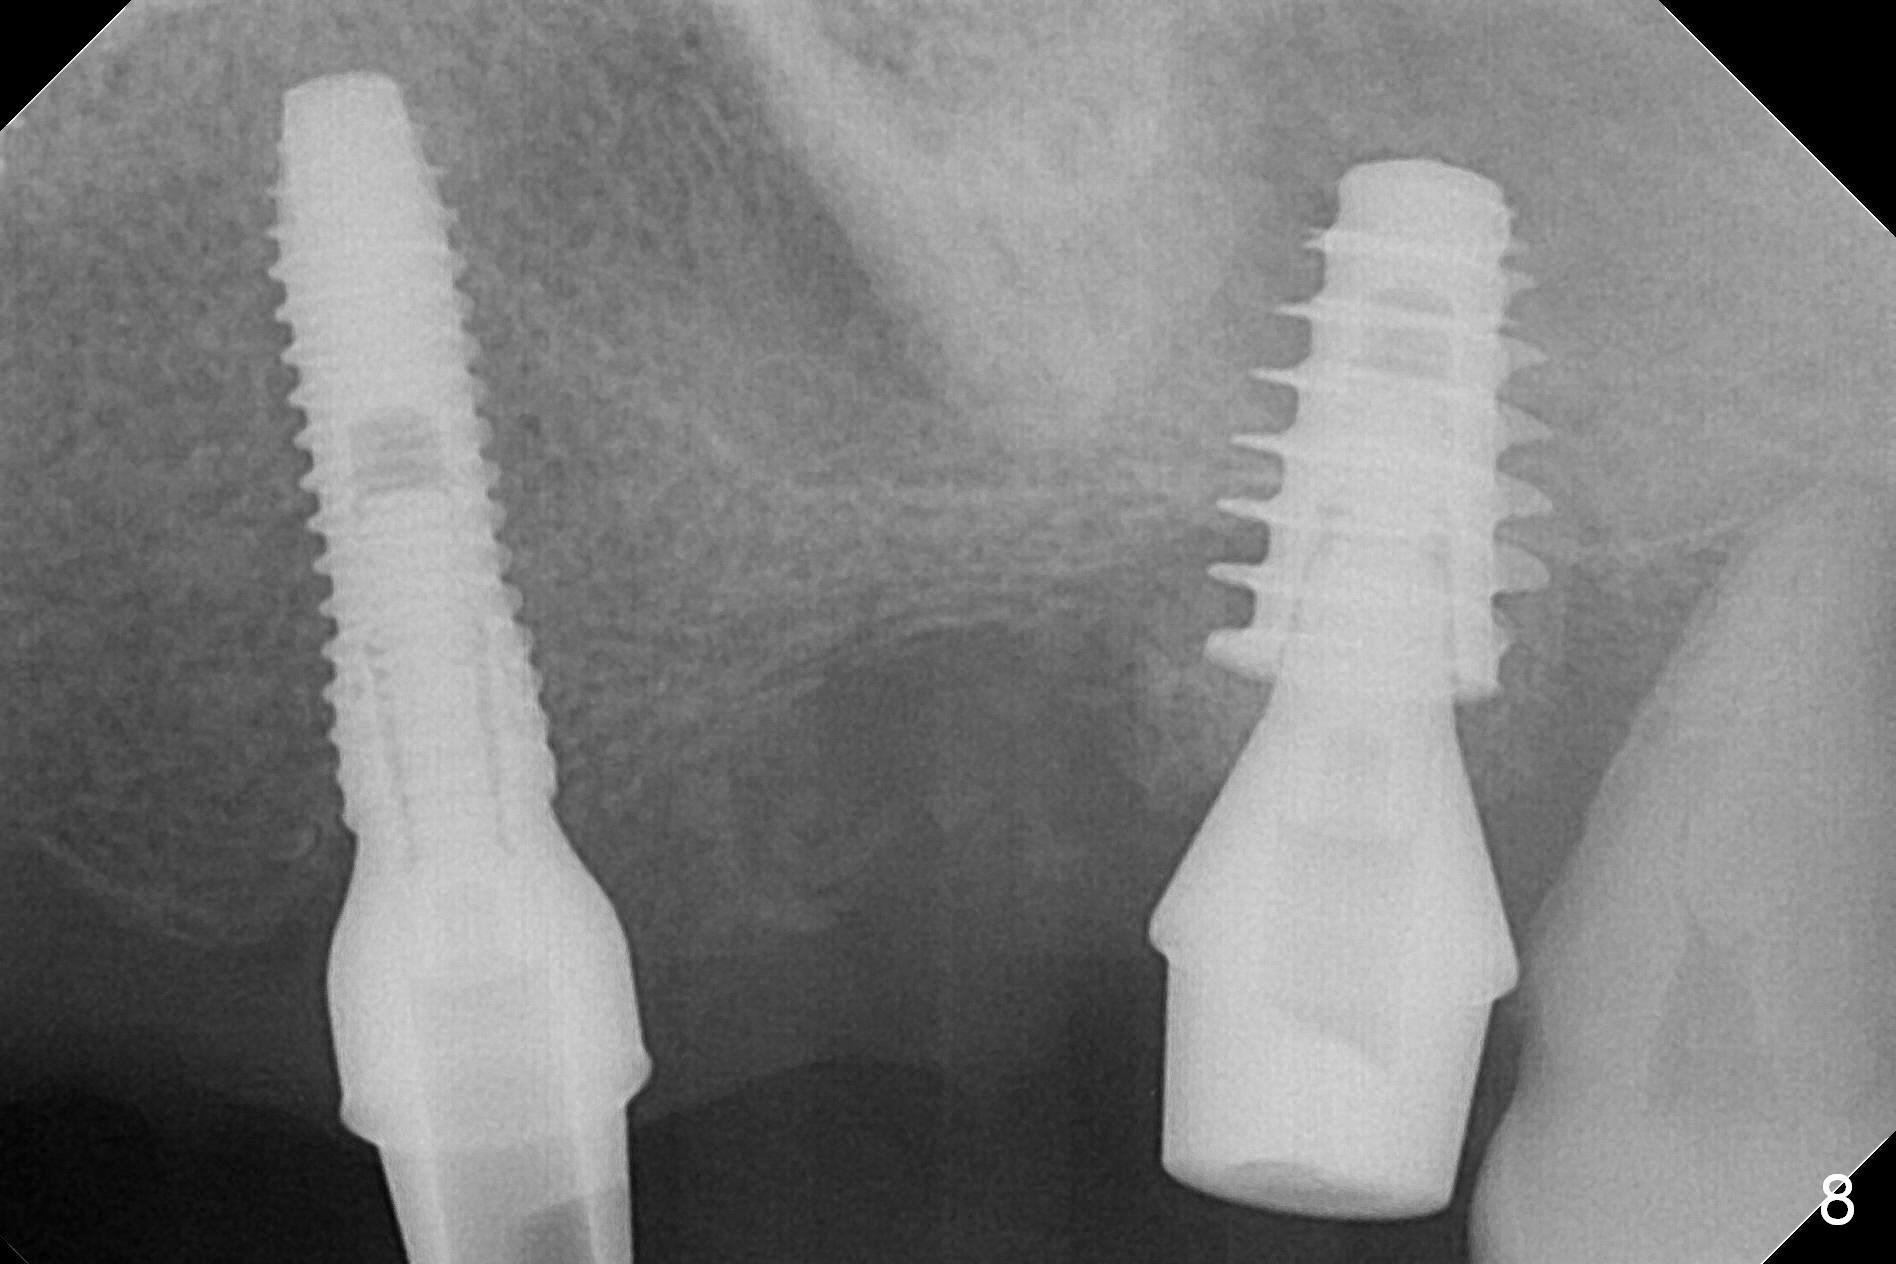

The posterior abutment of the 5-unit FPD, #15 is loose with the buccal roots extruded outside the sockets. The palatal socket is the appropriate site of immediate implant with the presence of the buccomesio-palatal walls, although short. The thinnest portion of the palatal socket is 1.6 mm (Fig.6 CBCT coronal section through the palatal root (P)). Magic Sinus Lifter cannot break through the sinus floor. UF drills are used to create osteotomy and sinus lift until 4.3 mm. A 5 mm tap drill is inserted without stability (Fig.1). A 5.5x9 mm IBS dummy implant achieves insertion torque of 10 Ncm, although it looks smaller (Fig.2) than the tap in Fig.1. After placement of PRF membrane and bone graft (allograft, autogenous bone and Osteogen, Fig.3 *), a 6x9 mm IBS implant is placed with insertion torque of 30 Ncm. It appears that the fins of the implant slice into the bone at high magnification for engagement. Following further placement of the implant, bone graft is packed into the distal portion of the socket (Fig.4 <). The thin fins extends into mesial and distal thicker bone (Fig.5 (CBCT sagittal view) *).

One month later, bone graft is placed mesiopalatal to the implant at #15 (Fig.7 *,8) while a 3.8x13 mm implant is placed at #13 following bone expansion (using Magic Split and Magic Expander 3.0 mm (abutment 5.5x4(5) mm). Another month later, the tooth #16 is extracted to create space for #15 restoration. Two weeks later the abutment at #15 is found to be unstable (2.5 months postop). Local oral hygiene is poor. The abutment is removed and a 6x4 mm healing abutment is placed with mild tenderness. It appears that the limited bone height is associated with low stability with CMC. Three months later (5.5 months postop), the implant seems to be stable (Fig.9,10). The implant remains stable clinically 7 months postop (Fig.11). The bone graft appears to mature and covers the abutment with provisional 24 months postop, the bony changes is related to the thick gingiva (Fig.12 ^).